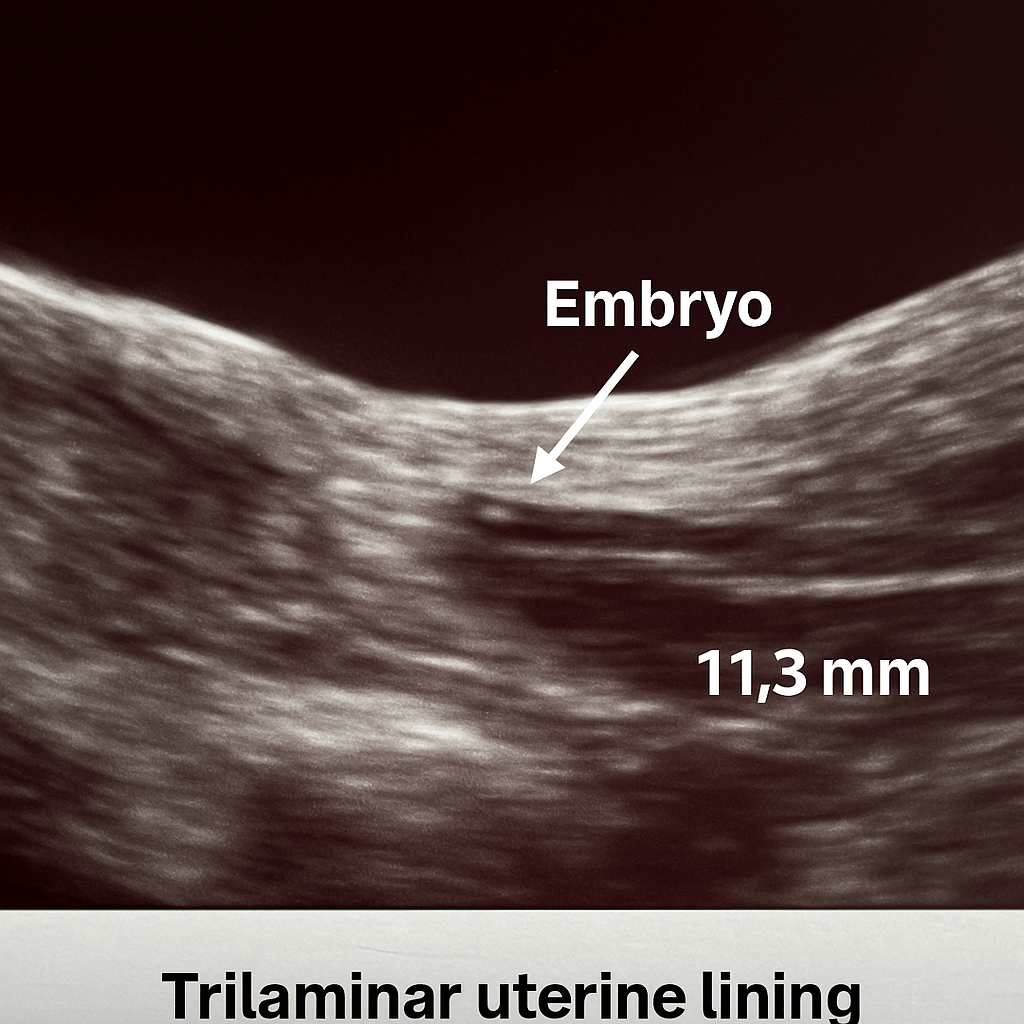

Watching the monitor, it felt like science and faith were merging to create a miracle. A tiny flash, and my embryo landed in the perfect spot. Amen. I took a deep breath, trying to hold onto that brief image and the possibility of what lies ahead. Thank you, God, for this hoped-for miracle.

Looking back on the TWW, it feels like a lifetime ago. We fought hard for those initial beta numbers, and the anxiety of those 14 days was immense. But today, the feeling is different. Today, I am 18 weeks pregnant. I’m officially a month into the second-trimester, and am gearing up for my anatomy scan. This little journal from August and September reminds me that every single day of fear and hope was worth it, because the pot of gold I sensed in the rainbow is now stretching and growing right beneath my hands.